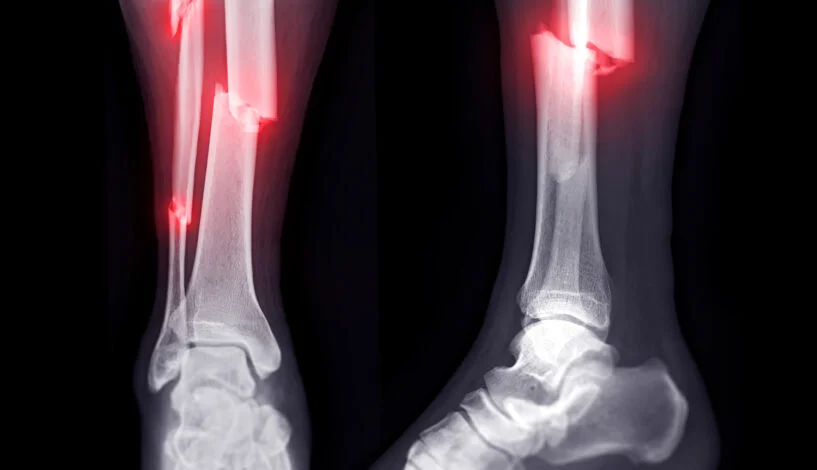

1st stage (fracture repair)

hematoma forms

2nd stage (fracture repair)

soft (fibrocartilaginous) callus forms

3rd stage (fracture repair)

hard (bony) callus forms

4th stage (fracture repair)

remodeling begins

open (compound) fracture

closed (simple) fracture

displaced fracture

transverse fracture

oblique fracture

compression fracture

greenstick fracture

spiral

communiated fracture